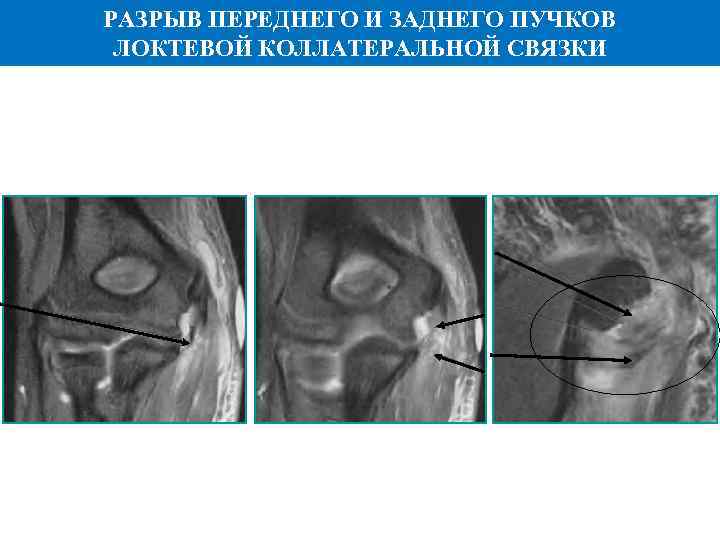

РАЗРЫВ ПЕРЕДНЕГО И ЗАДНЕГО ПУЧКОВ ЛОКТЕВОЙ КОЛЛАТЕРАЛЬНОЙ СВЯЗКИ

РАЗРЫВ ПЕРЕДНЕГО И ЗАДНЕГО ПУЧКОВ ЛОКТЕВОЙ КОЛЛАТЕРАЛЬНОЙ СВЯЗКИ